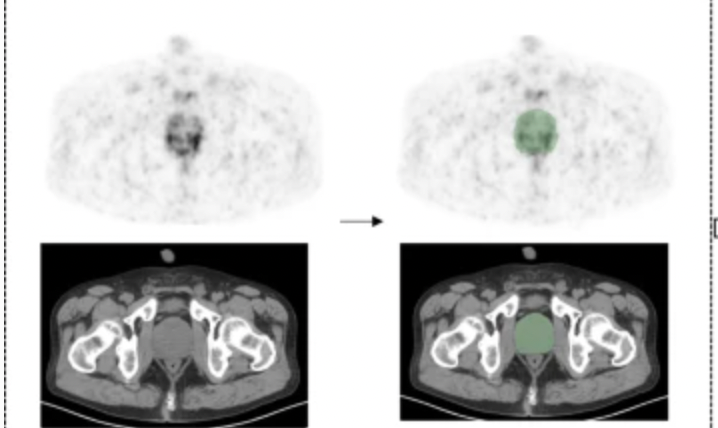

An emerging radiomics model, derived from 68Ga-PSMA-11 PET, reportedly offers a superior area under the curve (AUC) and higher sensitivity than radiologist assessment in detecting intraprostatic lesions via positron emission tomography/computed tomography (PET/CT) in patients with prostate cancer.

PSMA PET is highly robust in identifying prostate cancer lesions which are otherwise deemed unremarkable.